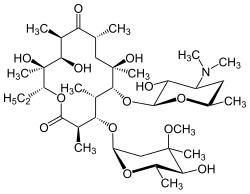

Os antibióticos da classe dos macrolídeos, principalmente a eritromicina, são eficazes no tratamento da panbronquiolite difusa quando administrados regularmente por um longo período de tempo.[8][9] Os fármacos preconizados incluem eritromicina, claritromicina e roxitromicina. A azitromicina também tem sido estudada e considerada igualmente eficaz, com uma minoria de pacientes descritos como "curados" e uma maioria relatando redução nos sintomas.[10] Os resultados bem sucedidos com o uso de macrolídeos na panbronquiolite difusa, e outras doenças pulmonares similares, decorrem da melhora de determinados sintomas através de imunomodulação (adequação da resposta imune), que pode ser conseguida com o uso dos antibióticos em doses baixas.[9] O tratamento consiste na administração oral diária de eritromicina por dois a três anos; um período longo, mas que tem sido demonstrado como capaz de melhorar drasticamente os efeitos da doença.[11] Isto se torna evidente quando um indivíduo em tratamento para panbronquiolite, entre uma série de critérios relacionados com a remissão da doença, apresenta uma contagem normal de neutrófilos no lavado broncoalveolar e uma gasometria arterial (exame que mede a quantidade de oxigênio e dióxido de carbono no sangue arterial) mostrando níveis de oxigênio dentro da faixa normal.[8][9][12] Uma pausa temporária na terapia com eritromicina pode ser, nesses casos, realizada, afim de reduzir a indução de Pseudomonas aeruginosa resistentes a macrolídeos.[8] No entanto, os sintomas geralmente retornam, e o tratamento terá de ser retomado. Apesar de altamente eficaz, a eritromicina pode não ser bem sucedida em todos os pacientes com a doença, especialmente naqueles com P. aeruginosa resistente a macrolídeos ou nos que não foram tratados precocemente e a panbronquiolite já progrediu para uma insuficiência respiratória.[9][12]

A administração de eritromicina em pessoas com a doença provoca grande redução na inflamação dos bronquíolos. Tal benefício é conseguido através da supressão, não só da proliferação de neutrófilos, como também da atividade de linfócitos, o que diminui a produção de secreções mucosas que obstruíam as vias aéreas.[8] Os efeitos antibióticos dos macrolídeos não estão envolvidos com a sua ação benéfica no sentido de reduzir a inflamação na panbronquiolite.[12] Isto é evidente porque a dosagem usada é muito baixa para combater uma infecção e mesmo nos casos em que há Pseudomonas resistente aos macrolídeos, a terapia com eritromicina ainda consegue reduz a inflamação.[8]

Uma série de fatores estão envolvidos na supressão da inflamação pela eritromicina e outros macrolídeos. Esses fármacos são especialmente eficazes em inibir a proliferação de neutrófilos, diminuindo a capacidade de interleucina 8 e do leucotrieno B4 em atraí-los. Os macrolídeos também reduzem a eficiência de moléculas de adesão que permitem que os neutrófilos penetrem entre pequenos espaços no tecido bronquiolar. A produção de muco nas vias aéreas é um dos principais responsáveis na morbidade e mortalidade de doenças respiratórias como a panbronquiolite difusa. E o uso de eritromicina, além de reduzir significativamente a inflamação na doença, também ajuda a inibir a produção excessiva de muco.[13]